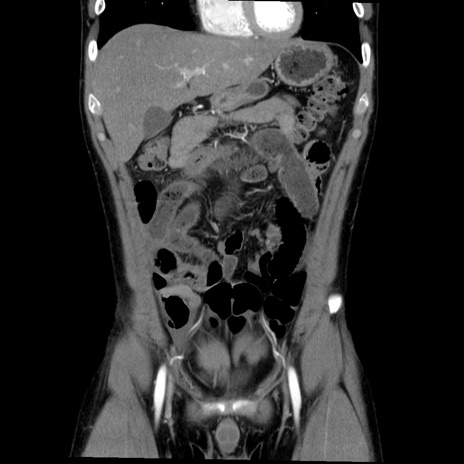

症例36(冠状断像)

【症例】20歳代 男性

【主訴】心窩部痛

【現病歴】今朝より上腹部痛あり。一旦軽快していたが再度出現したため救急要請。昨日夕に白身の魚を含む刺身を食べた。

【身体所見】BP 136/89mmHg、HR 74/min、BT 37.0℃、腹部:膨満、軟、心窩部に圧痛あり。反跳痛なし、筋性防御なし、腸雑音やや亢進あり。

【データ】WBC 17700、CRP 0.48